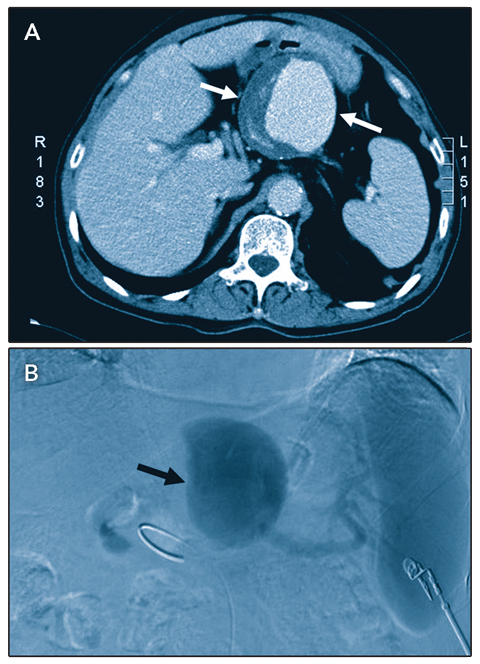

A 70-year-old man had a 1-year history of intermittent abdominal distension. Abdominal ultrasound examination showed a cystic lesion near the pancreas. Contrast computed tomography scans showed a large aneurysm (Figure A, arrows) about 80 × 70 mm in size. Angiography of the coeliac and splenic arteries confirmed the diagnosis of a giant splenic artery aneurysm (Figure B, arrow). The aneurysm was surgically ligated and excised, and the spleen was removed. The postoperative course was uneventful. Splenic artery aneurysms larger than 80 mm are rare.1 Open ligation or embolisation should be considered for symptomatic aneurysms, aneurysms ≥ 2 0 mm in size, or any splenic artery aneurysm in a woman of childbearing age.2